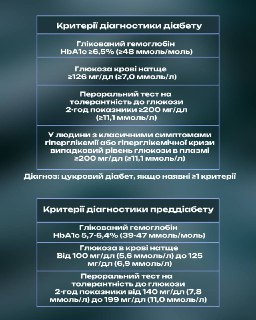

Медикаментозна терапія ЦД 2-го типу 🍬